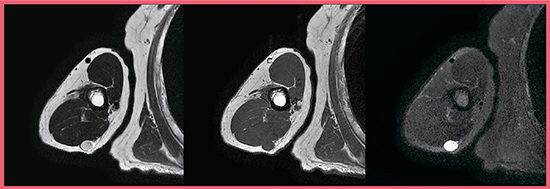

症例1は,神経鞘腫である(図3)。

通常は撮像が困難な上腕でも,Regional RF Shimmingによりきわめて均一な画像が得られている。

図3 症例1:Regional RF Shimmingを適用した神経鞘腫の画像